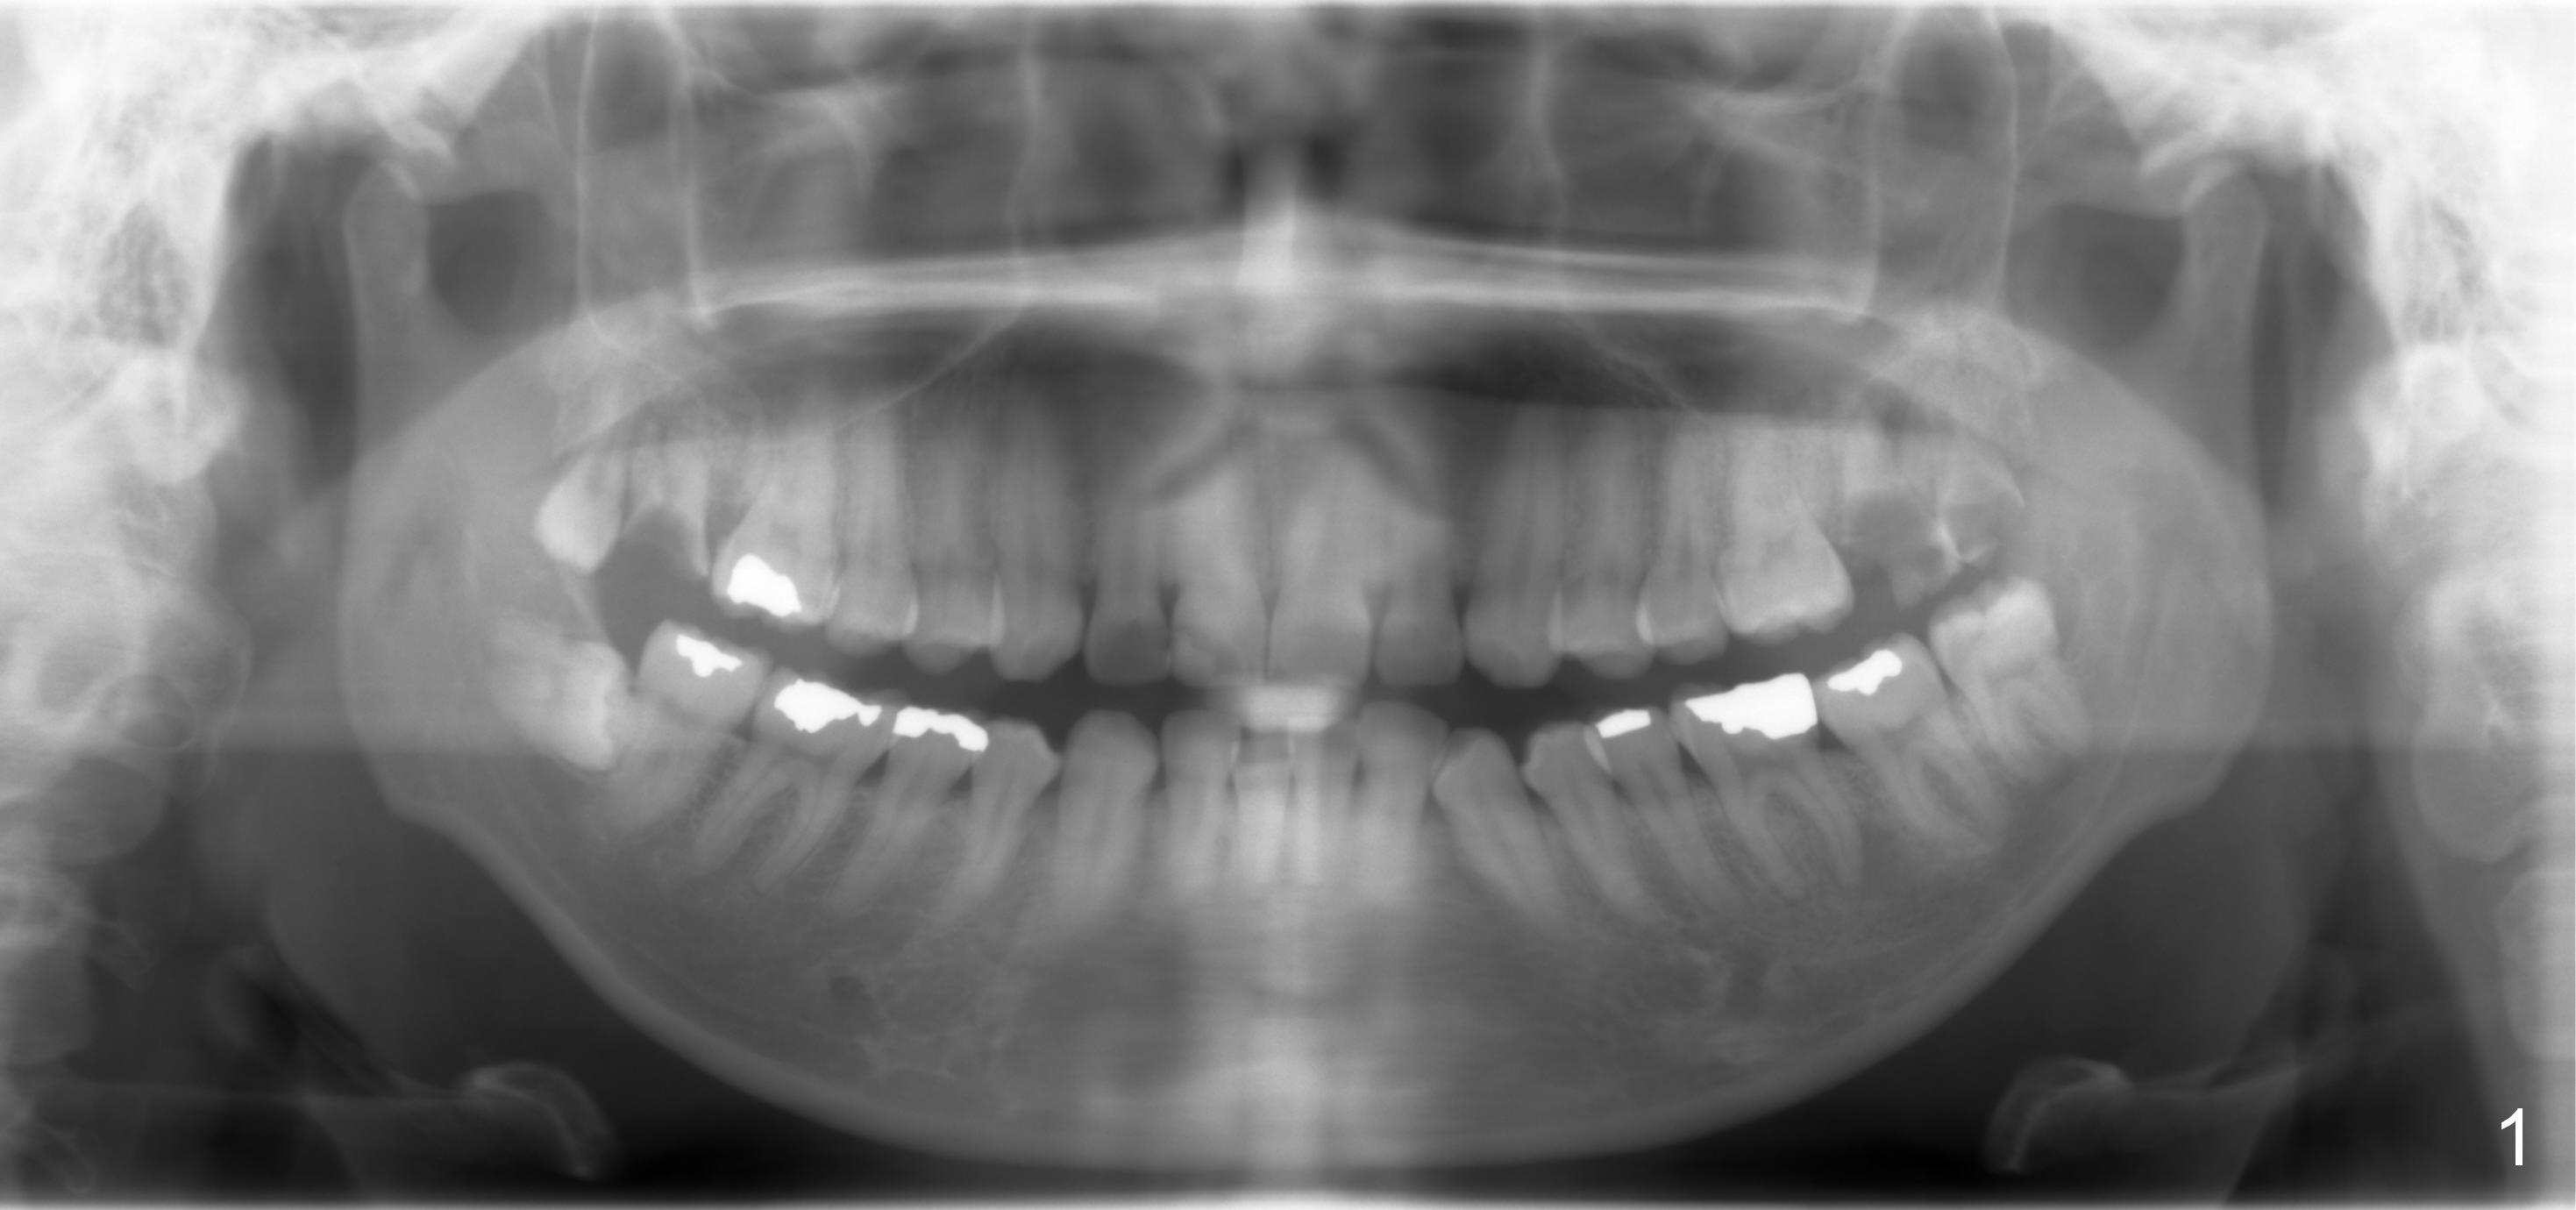

The panoramic X-ray (Fig.1) was taken on 12/12/2011 when the teeth #15 and 16 were extracted. The teeth #1 and 2 were removed half a year later. Bitewings (Fig.2-5), PAs (Fig.6,7) and upper occlusal mirror photo were taken on 02/11/2015. Pay attention to Fig.2.